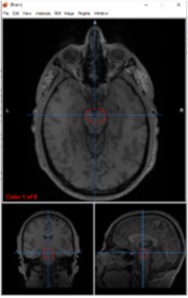

amygdalae

emotional processing, fear conditioning, and memory

amygdala

primary center for emotional processing, fear conditioning, and threat detection